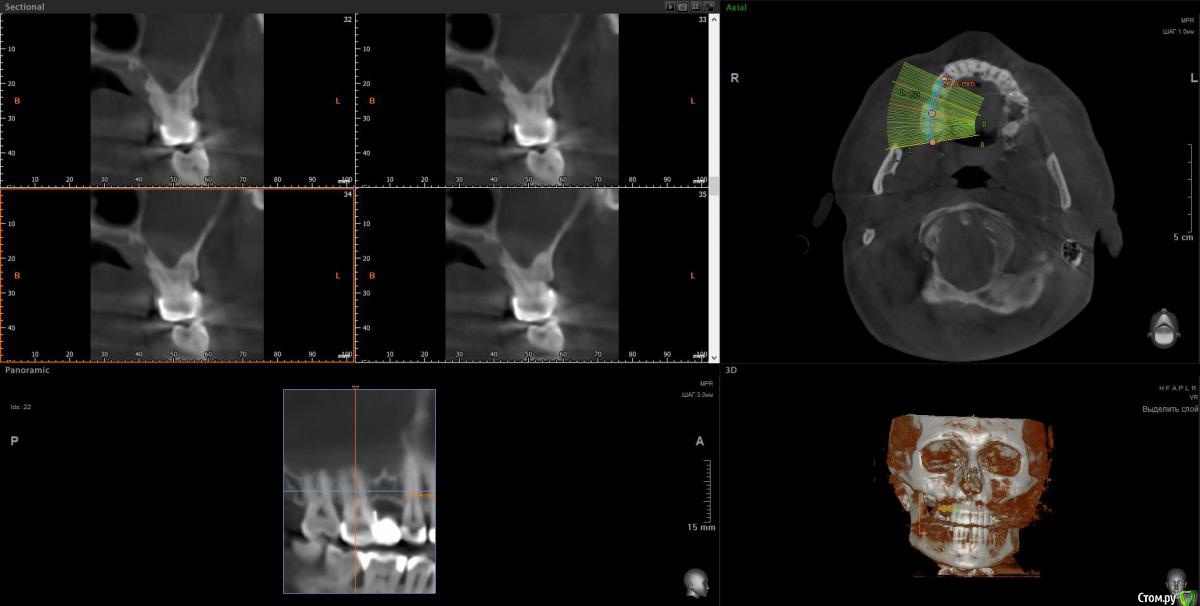

wladdX Опубликовано 5 марта, 2019 Поделиться Опубликовано 5 марта, 2019 Корональная проекция Сагиттальная справа Сагиттальная слева 16 26 28 Ссылка на комментарий

kramer Опубликовано 5 марта, 2019 Поделиться Опубликовано 5 марта, 2019 В общем скачал я КТ. Что касается зуба 26, да, там есть признаки воспаления вокруг корней, лечить / удалять зависит от состояния тканей зуба и возможностей врача. Но лично мне не кажется, что этот зуб играет главную роль в возникшем гайморите. Обратите внимание, в области 8 зуба (см. срез) внутри пазухи есть некий очаг, содержащий неоднородные по плотности элементы (более светлые включения, а выше пузырьки воздуха). Снимок не особо четкий, но такое ощущение, что в области 8 зуба вообще нарушена целостность боковой стенки пазухи. Кроме того, с правой стороны все зубы в порядке, а явления гайморита тоже имеются (там вообще почти вся пазуха забита). Соустья с носом закрыты. В общем, в данной ситуации я бы более детально обследовал 8 зуб, если там все нормально, то пусть ЛОРы эндоскопически лезут в пазухи и убирают это все. Ссылка на комментарий